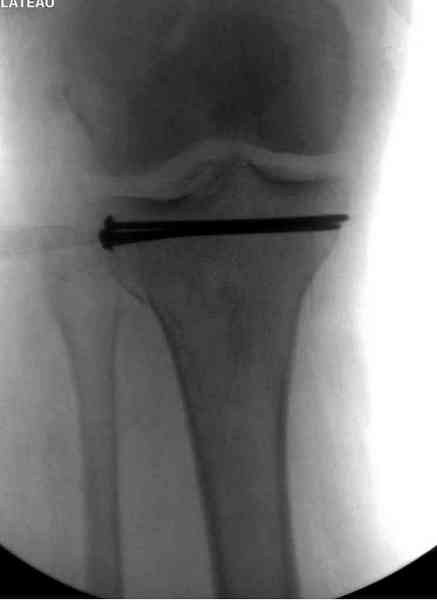

Основная задача в лечении околосуставных переломов является создание солидного базиса в субхондральной зоне. Пластина подпорка (Butress) или субхондральные перкутанные шурупы в виде плота (Raft) для ранних движении.

У больного двухстороннее повреждение, ограничен в нагрузке не менее 8-10 недель. После односторонней фиксации будет активным, хотя бы в пределах койки. Без спешки дождаться улучшения кожных покровов, и аппаратом Илизарова в комбинации с шурупами или спицами, из мини-доступов.

Отсутствие материала не причина не делать хорошую репозицию, или лучше перевести больного туда, где больше возможностей. Александр прав, вместо пластины предпочтительным будет фиксировать аппаратом Илизарова.